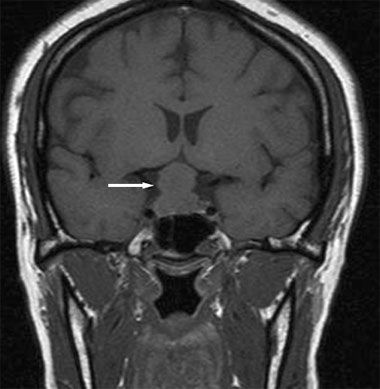

The patient was afebrile. Blood pressure was 120/82 mm Hg. Mild nystagmus was present on horizontal gaze. There were no other pertinent physical findings or abnormal laboratory results. An MRI scan of the head revealed a 2.2-cm suprasellar mass with compression of the optic chiasm (arrow).

A pituitary adenoma was suspected, and the patient underwent transsphenoidal resection of the pituitary gland. Diabetes insipidus developed secondary to the pituitary gland resection. She responded appropriately to a course of desmopressin and was discharged.

Histopathological examination of the pituitary gland revealed lymphocytic hypophysitis, without evidence of pituitary adenoma. Lymphocytic hypophysitis-an autoimmune disorder in which lymphocytes infiltrate and cause destruction of the anterior pituitary gland-is associated with pregnancy and can occur anytime from the late prenatal period until 1 year postpartum. Although the affected pituitary gland initially enlarges, it eventually atrophies and fibrosis develops. Biopsy of the gland reveals lymphocyte and plasma cell infiltration.1 Rarely is a lymphocytic hypophysitis mass found to be larger than 1.5 cm.2